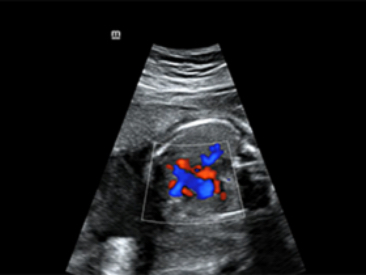

Obrazy kliniczne